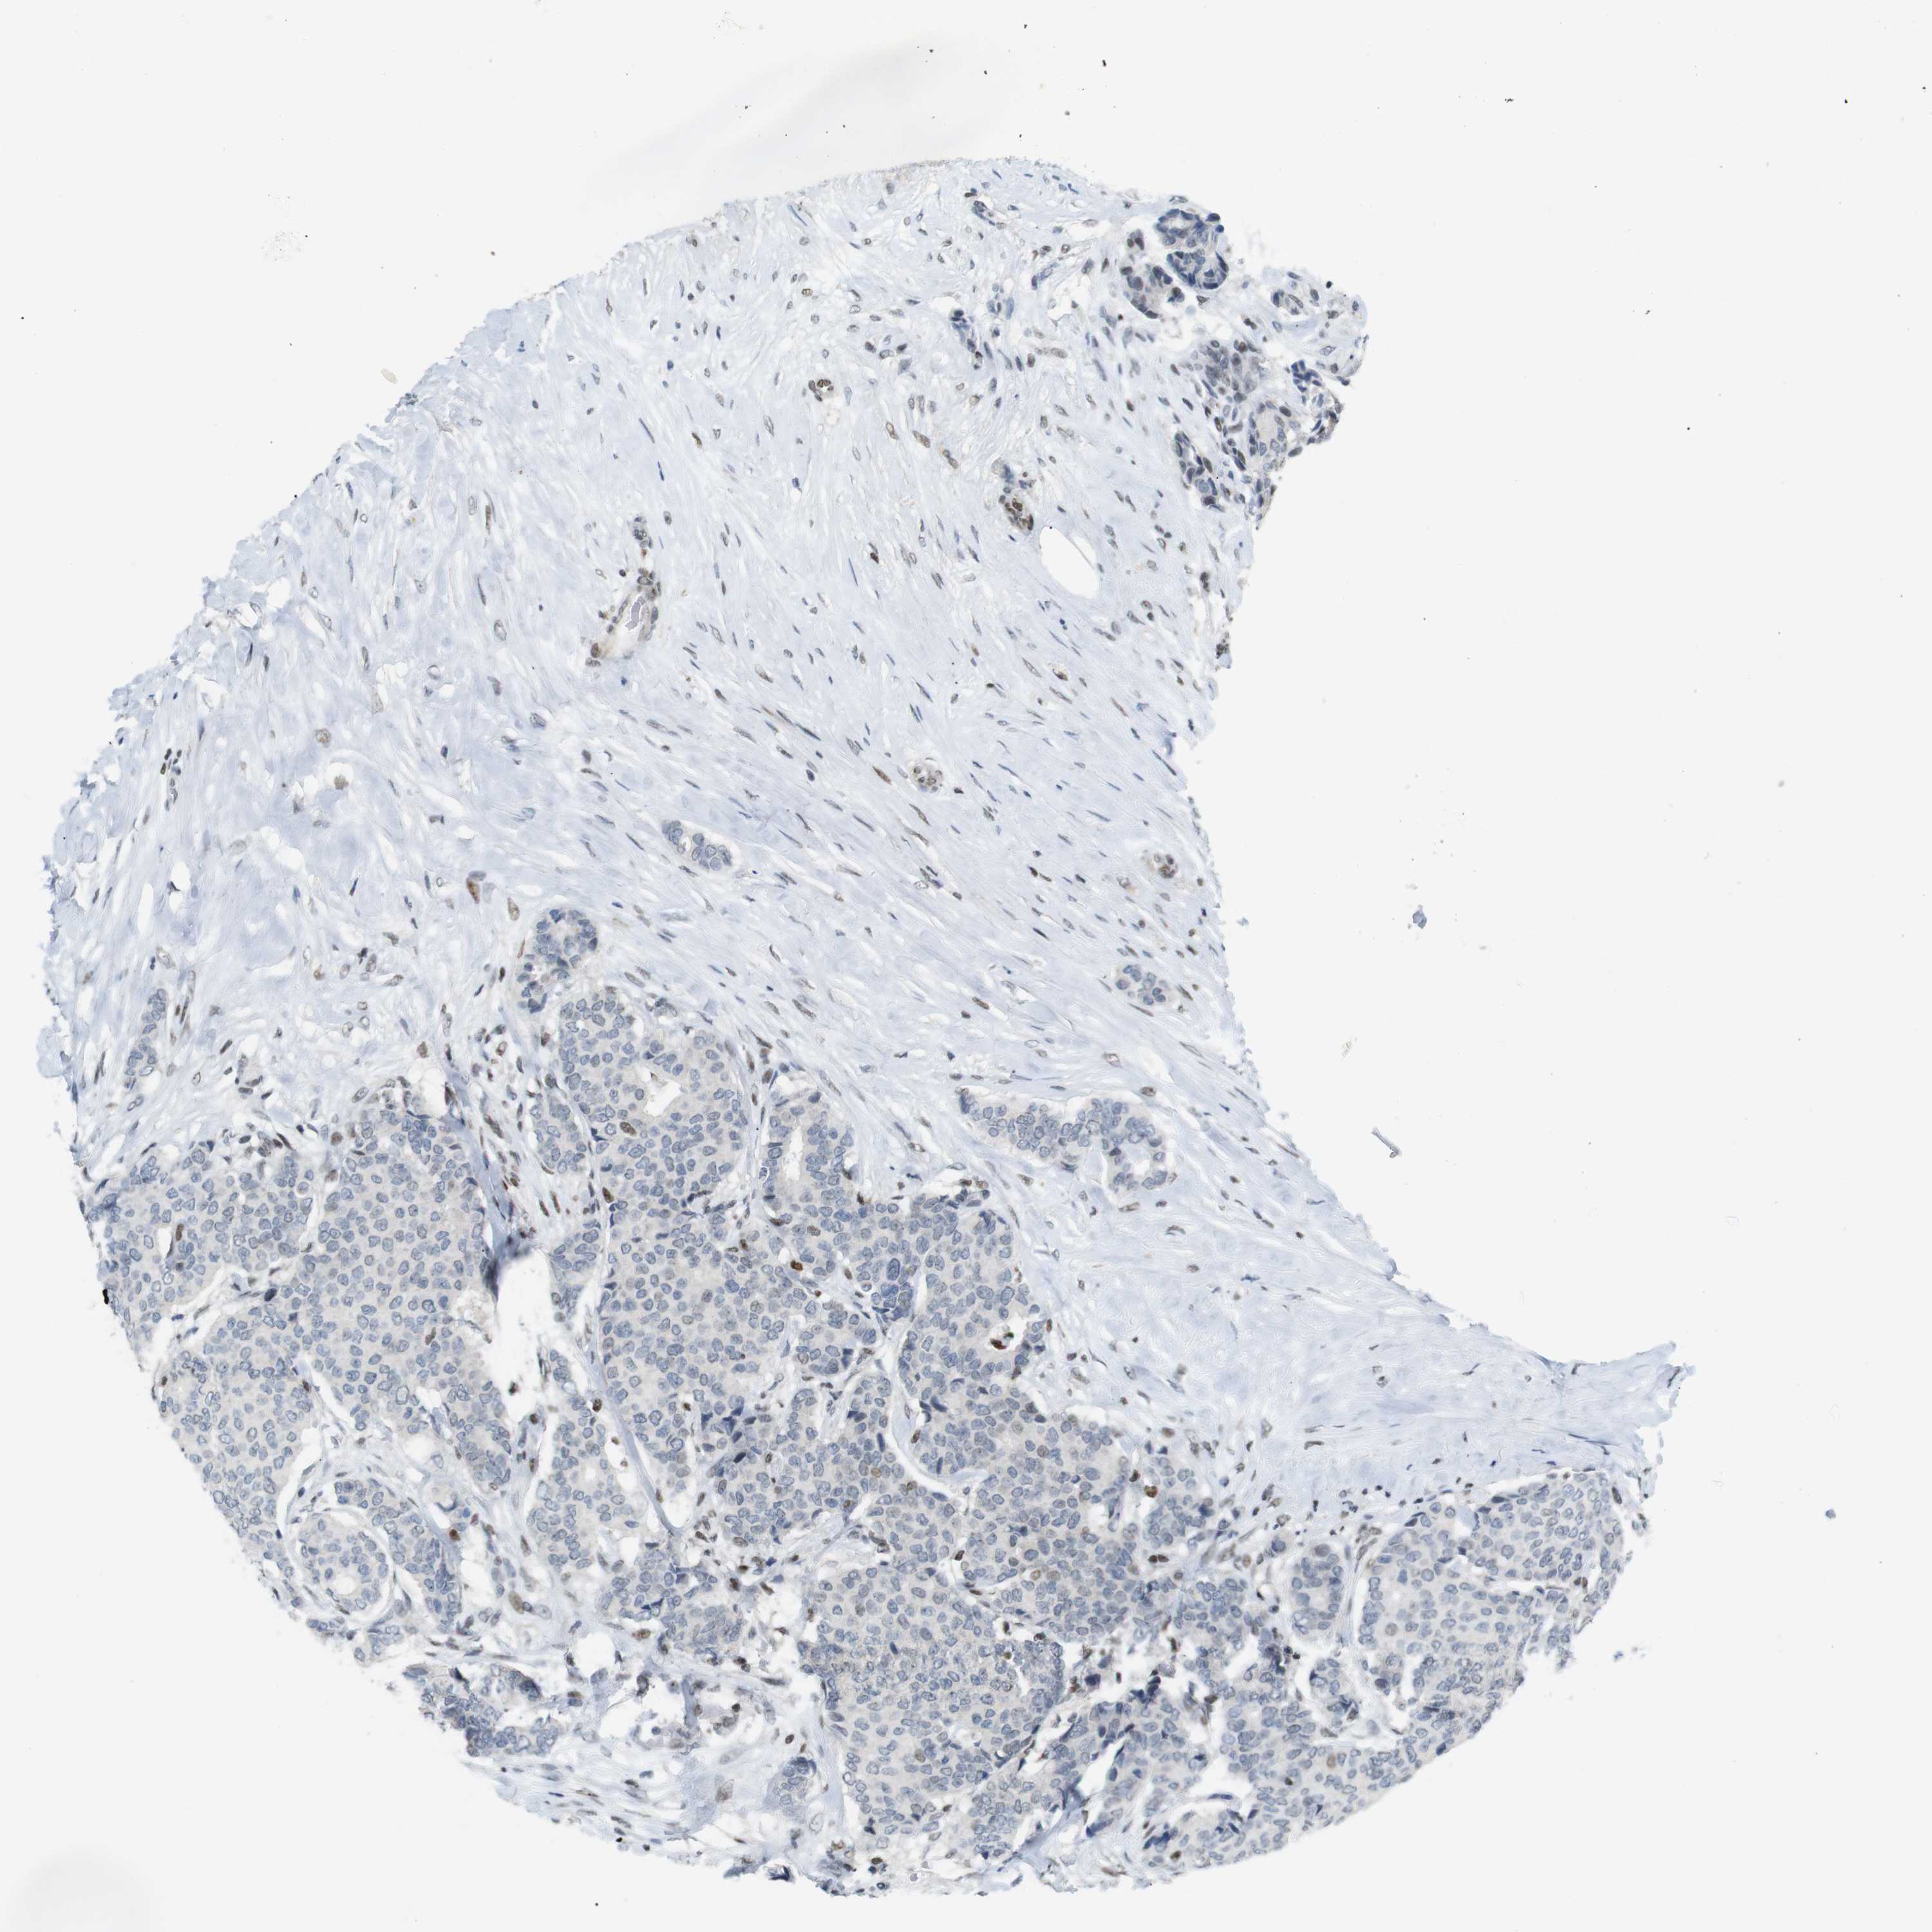

BRCA TCGA BRCA VALIDATION PROTEIN EXPRESSION

RIOX2 is potential prognostic, high expression is unfavorable in Breast Invasive Carcinoma (TCGA)